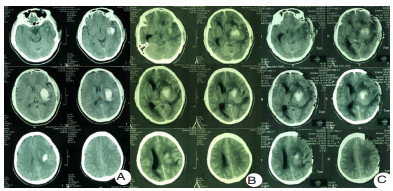

在严重脑损伤的病理生理状态下,尤其是严重的水盐电解质紊乱或感染炎症的状态下,液体的分布将极大的改变全身系统有效血容量,也将影响脑血流灌注而导致影响脑功能。对于神经危重症患者,包括急性中重度颅脑损伤和严重脑卒中患者,急性期需要甘露醇、甘油果糖等脱水渗透性治疗控制颅内压;存在不同程度的感染和全身炎症反应综合征,尤其是严重脓毒血症时,输入的部分液体通过毛细血管的组织间隙渗漏,液体存在异常分布,炎症的严重程度与体液异常分布的程度显著相关。高热、气管切开、呼吸机的使用、植物神经功能紊乱时的交感过兴奋发作等也将导致体液通过呼吸道和体表大量隐性丢失。这些液体异常的分布和丢失目前无法做到精准的测量,显著增加液体精准管理的困难和可能影响患者的预后。临床上,目前在国内神经重症管理中更多倾向于限制液体的策略,以减少肺水肿和心功能不全等并发症,但在缺乏严格有效血容量的监测下,可能导致严重的继发脑血缺血并发症(图 1)。该例左侧基底节脑出血患者入院时神志清楚,经过12 d的保守治疗后,在没有血肿扩大的情况下,因为过度液体负平衡导致的严重继发脑缺血后形成脑疝而需要开颅去骨瓣减压。

| A:第1天,神志清楚遵嘱;B:第23天,脑疝;C:第23天,开颅左侧去骨瓣术后,脑缺血进一步加重 图 1 患者高血压自发性脑出血CT结果 |